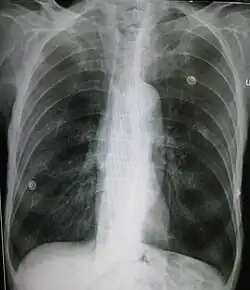

Im Röntgenbild (Röntgen-Thorax) zeigt sich das Lungenemphysem in einer verminderten Dichte des Lungengewebes. Zudem kann ein Tropfenherz ausgebildet sein.